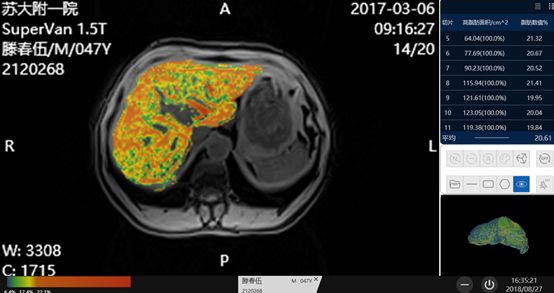

组织分割 区域量化

脂肪与铁双定量的技术更新至2.0版本,增加了组织区域自动分割,多区域量化的功能,后处理系统可以自动识别肝脏组织,并且剔除掉脉管系统,用不同的颜色来标注不同程度脂肪肝的区域,同时可量化每个层面重度脂肪肝的面积大小,并计算出平均的脂肪含量百分比,帮助我们更加直观的观察脂肪含量的情况。